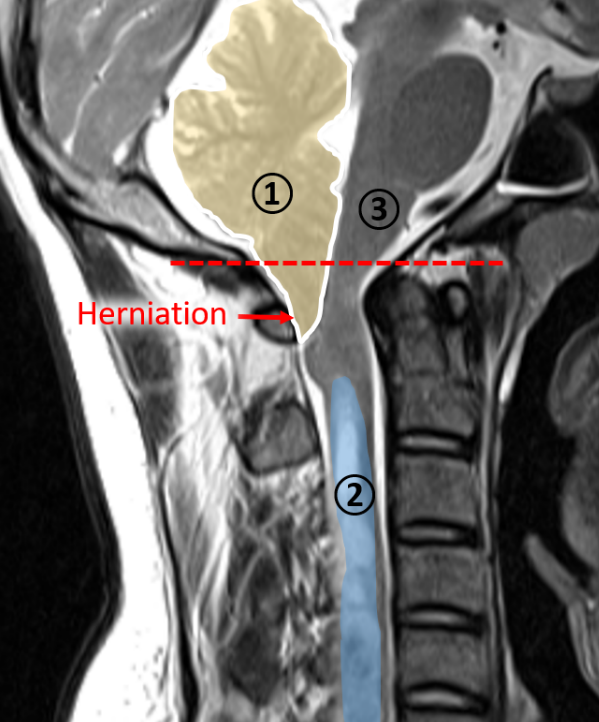

In Chiari type 1 malformation a local obstruction of the CSF flow is caused by the lower part of the cerebellum (tonsils), which herniates and extends below the foramen magnum, the opening in the skull base that enables brain-spinal cord connection, as shown in Figure 1. The obstruction is thought to be the cause of fluid accumulation inside the spinal cord (known as a syrinx), which is found in about 66% of patients with Chiari type 1 malformation. The syrinx may evoke severe motor and sensory symptoms by stressing the spinal neurons and eventually results in irreversible neural damage [2]. Currently, the only treatment is an invasive surgical procedure, which aims to remove the disturbance of the CSF flow. Because the procedure is invasive with a high risk for complications and variable outcomes, the interest raises to explore new treatments [3].

Figure 1: T2 MRI image of a patient with Chiari type 1 malformation showing the herniation of below the foramen magnum (red line) of the lower part of the cerebellum (1), the fluid-filled cavity (2), and the brainstem (3).